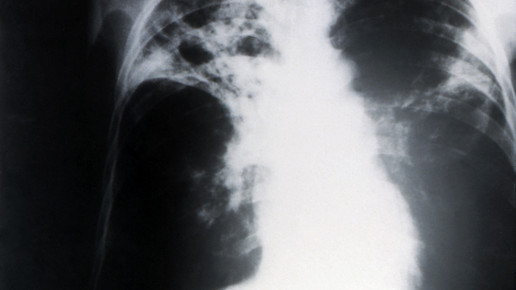

Weltweit starben 2013 rund 1,5 Millionen Menschen an den Folgen von Tuberkulose. Bei knapp 500.000 Menschen entwickelte sich im selben Jahr eine Multiresistenz, die mangels therapeutischer Alternativen in weniger als der Hälfte der Fälle behandelbar war.